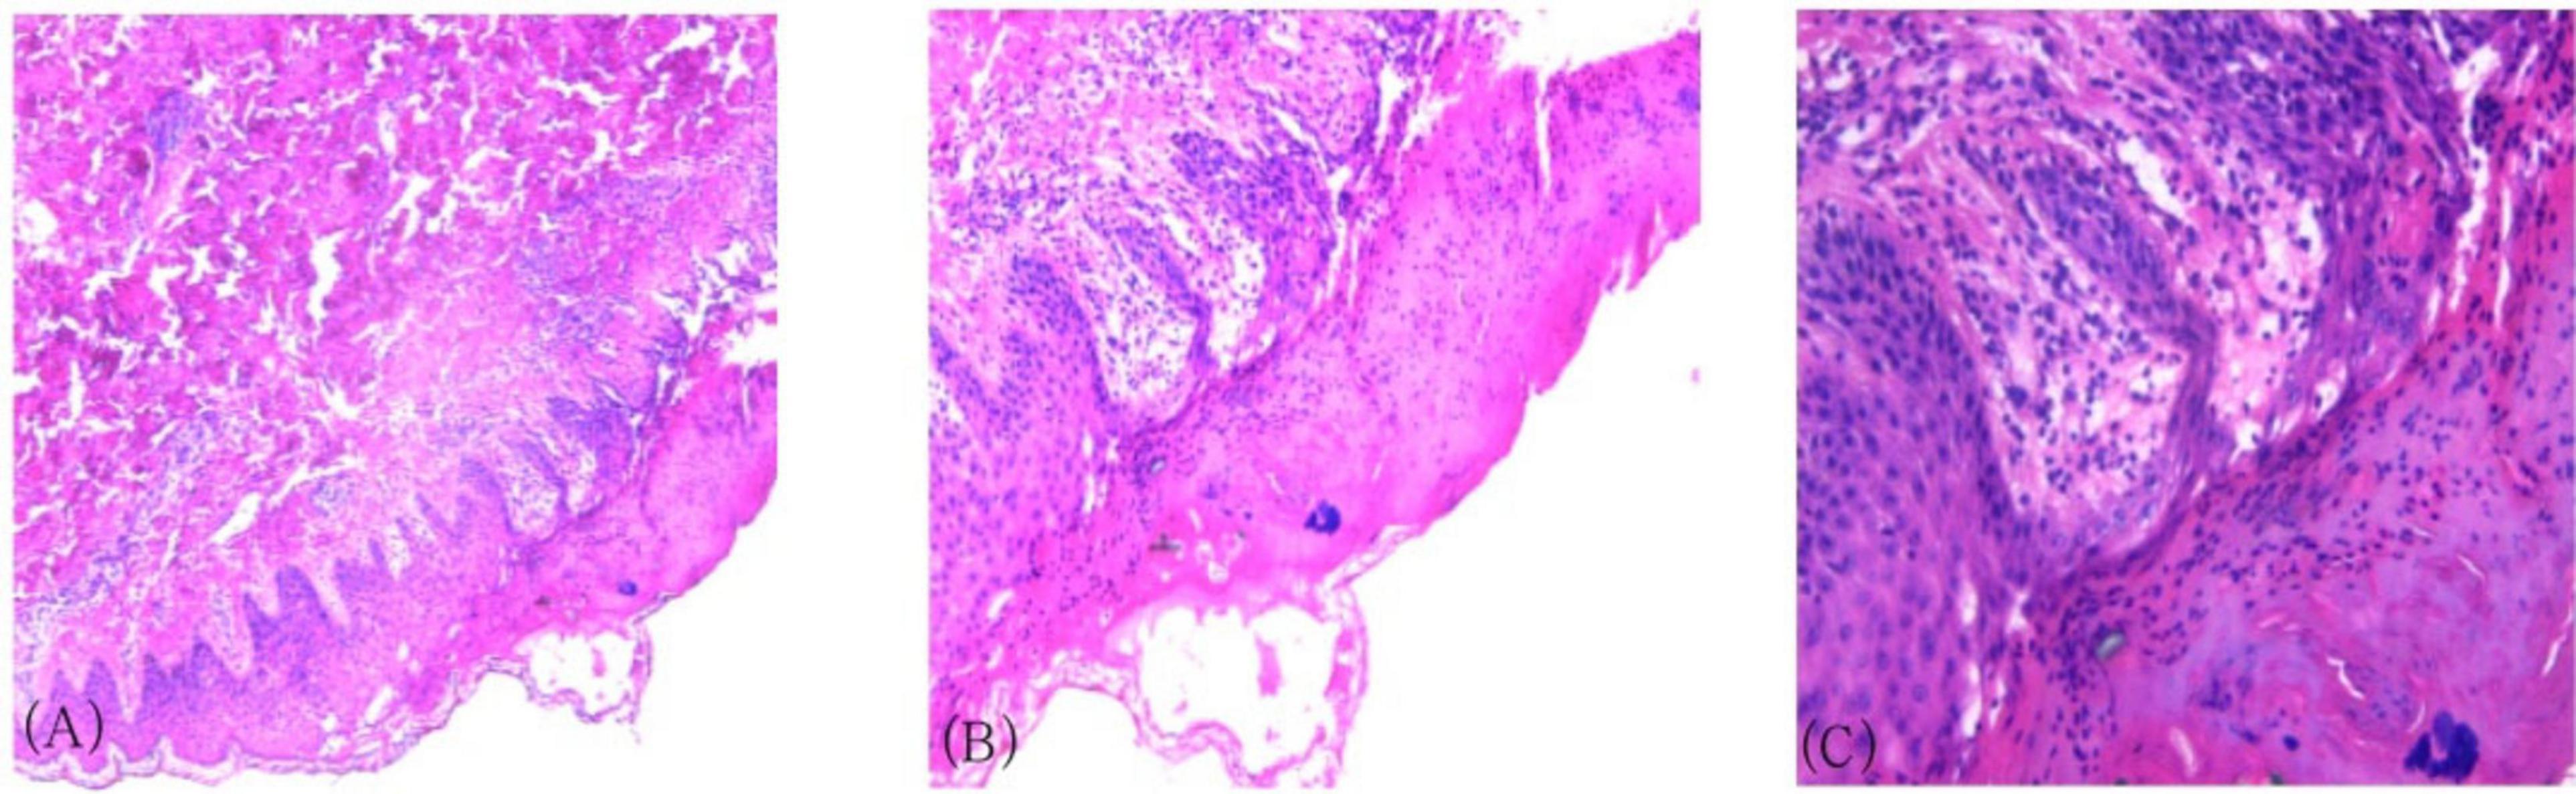

A 27-year-old male patient presented with erythema, papules, vesicles, and pruritus, with recurrent episodes lasting more than 2 years. Approximately 2 years ago, he developed scattered papules, nodules, and vesicles on his body without any obvious triggers. These lesions were accompanied by severe itching that affected his daily activities and sleep. Scratching led to vesicle rupture and crust formation. Over time, the rash spread throughout the body, leading to hospitalization at several medical facilities, Following a skin biopsy, PLEVA was diagnosed. Initial treatment with tofacitinib, thalidomide tablets, compound glycyrrhizin tablets, methotrexate, ultraviolet phototherapy, and other treatments, resulted in mild improvement. One year ago, the patient experienced a recurrence of symptoms, again without any obvious trigger. The rash worsened, with marked pruritus and pain. He was admitted to our department, and a second skin biopsy confirmed the diagnosis of PLEVA. Treatment with immunoglobulin, methylprednisolone, sodium succinate, anti-infection therapy, and immunomodulation led to clinical improvement. After discharge, the patient continued regular oral treatment with oral methylprednisolone tablets, cyclosporine capsules, and Tripterygium wilfordii tablets. His symptoms initially improved with these treatments; however, the rash repeatedly recurred. Four days before his most recent hospitalization, the patient experienced symptom exacerbation following a common cold. This episode was characterized by the appearance of numerous papules, nodules, and vesicles on the neck, chest, abdomen, and limbs, with significant itching, along with headache and nasal congestion. The patient had a history of atopic dermatitis. Systemic examination showed stable vital signs. There was a cushing syndrome due to the patient’s prolonged corticosteroid use; however, no other abnormalities were found. Dermatological examination revealed numerous scattered, round, red patches and papules ranging in size from mung bean- to soybean-sized on the head, face, trunk, and limbs, along with a few scattered blisters. The blister walls were tense, the blister fluid was clear, and some lesions ruptured, with crusting and blood scabs. The body also had numerous scattered point- and line-shaped scratch marks. No obvious pustules or hyperplasia were observed. Scattered hyperpigmentation and acne-like scarring were observed after healing (Figures 1A, C, E, G). Laboratory test results were as follows: White blood cell count, 18.81 × 109/L; lymphocyte percentage, 8.60%; eosinophil percentage, 15.70%; absolute neutrophil count, 13.30 × 109/L; and absolute eosinophil count, 2.95 × 109/L. Allergen testing indicated a positive reaction to house dust mites, egg white, and wheat. A total immunoglobulin E (IgE) level of 97,500 IU/mL was found 2 years ago; at admission to our department, the level exceeded 1000 IU/mL and was retested after 2 months of using stapokibart. Serological testing was positive for Epstein-Barr virus (EBV) and varicella-zoster virus (VZV) antibody IgG. Regarding the lymphocyte count, the natural killer cell (CD16 + 56) count was 79.97 cells/μL, and the B lymphocyte percentage (CD19) was 19.17%. Kidney function testing indicated a uric acid level of 502 μmol/L. Liver function tests showed no significant abnormalities. Skin histopathology of the left arm showed hyperkeratosis of the epidermis, with infiltration of inflammatory cells in the stratum corneum, localized thickening of the stratum spinosum, liquefaction degeneration of the basal layer cells, superficial dermal edema, and perivascular infiltration with endothelial cell swelling (Figures 2A–C). Based on the patient’s clinical presentation and pathological results, the patient was diagnosed with PLEVA.

FIGURE 2

Histopathological results of the skin on the left arm. (A) Hyperkeratosis of the epidermis, inflammatory cell aggregation in the stratum corneum, localized acanthosis in the stratum spinosum (HE × 40). (B) Liquefactive degeneration of basal layer cells, superficial dermal interstitial edema (HE × 100). (C) Perivascular lymphocytic infiltration with endothelial cell swelling (HE × 200).